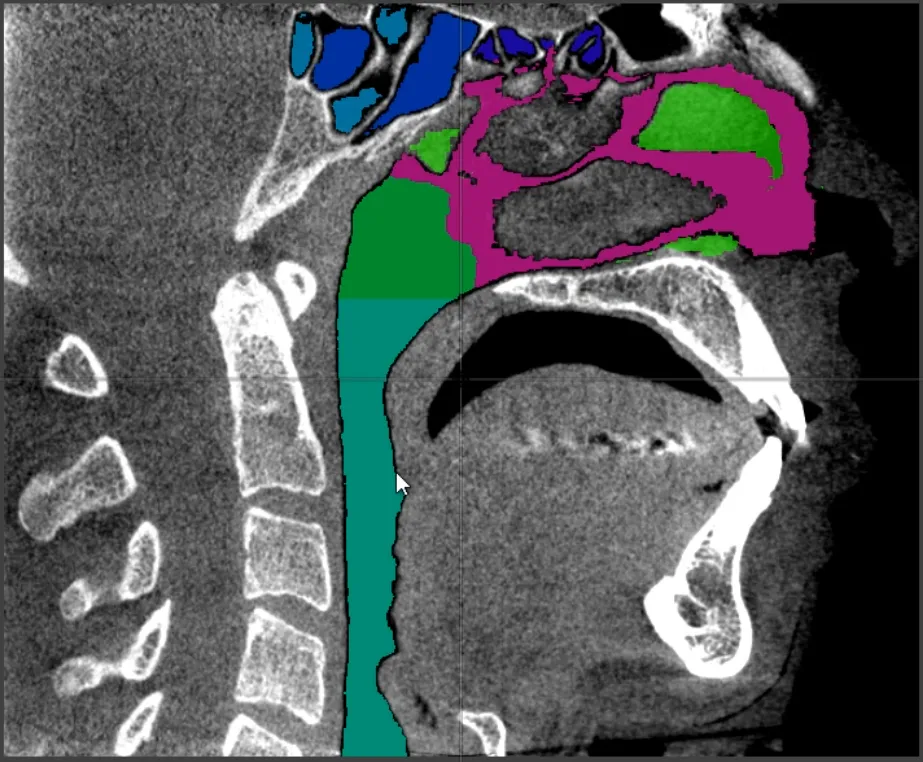

X-ray Cone Beam CT (CBCT) sagittal slice view of segmentation of human airway anatomy